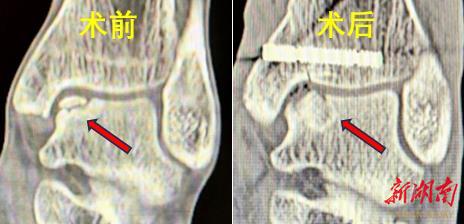

38岁的蒋先生和43岁的潘女士,均因踝关节扭伤导致距骨软骨损伤,保守治疗后疼痛反复,连日常行走都受影响。经湘雅三医院骨科足踝团队检查,两人被确诊为“距骨骨软骨损伤(HeppleIII型及V型)”——这类损伤因软骨自我修复能力差,一直是临床治疗难题。

“以往治疗要么用异体材料,要么取自身非负重区软骨,可能带来排斥或供区损伤。”主刀医生张克祥副主任医师介绍,本次手术创新采用“自体髂骨骨膜-骨栓移植”,同时定制3D打印导板实现精准截骨:先通过关节镜清理病灶,再借助导板精准显露损伤区,从患者髂骨提取带骨膜的骨栓植入损伤处,全程避免了异体排斥和供区软骨损伤,且骨膜含有的生长因子能加速修复。